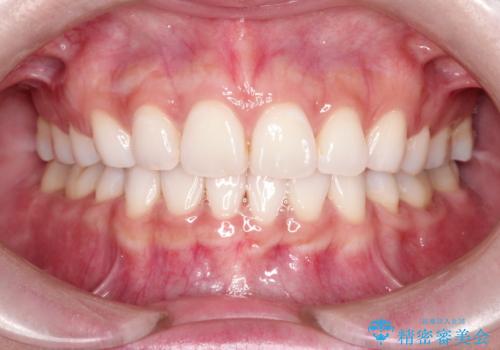

口が閉じにくい 口ゴボの抜歯矯正による改善

口元を下げて口唇を閉じやすくする場合、抜歯矯正をお勧めさせていただくことが多いです。

治療前には必ず患者様とよく相談させていただき、どのようなゴールにするか、それにはどんな治療が必要かをご理解していただいたうえで、治療を開始いたします。